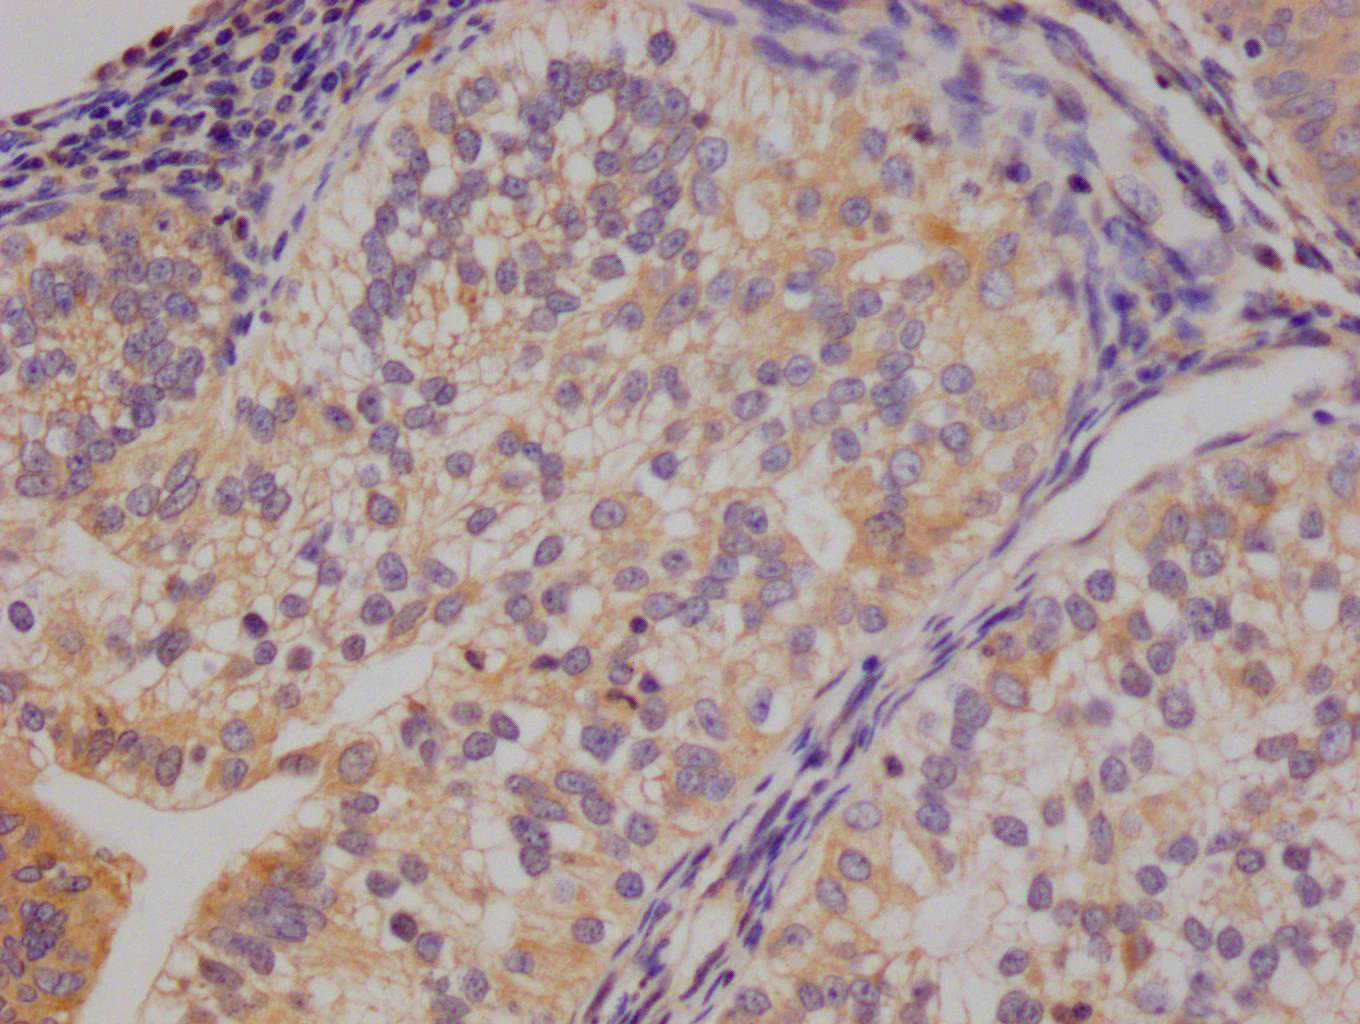

Immunohistochemistry of paraffin-embedded human prostate cancer using CSB-PA138304ESR2HU at dilution of 1:100